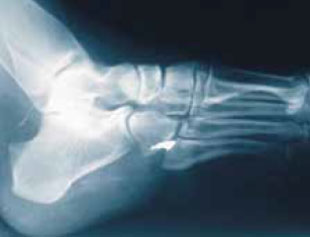

Если инородное тело находится неглубоко, особенно над точкой опоры (в ладонной поверхности кисти, в подошве ступни, в области локтевого сустава и т. д.), оно может причинять сильную боль (рисунок 10). Извлечение можно производить в плановом порядке после заживления острой травмы.

Рисунок 10. Металлический осколок находится в точке опоры – в подошве ступни